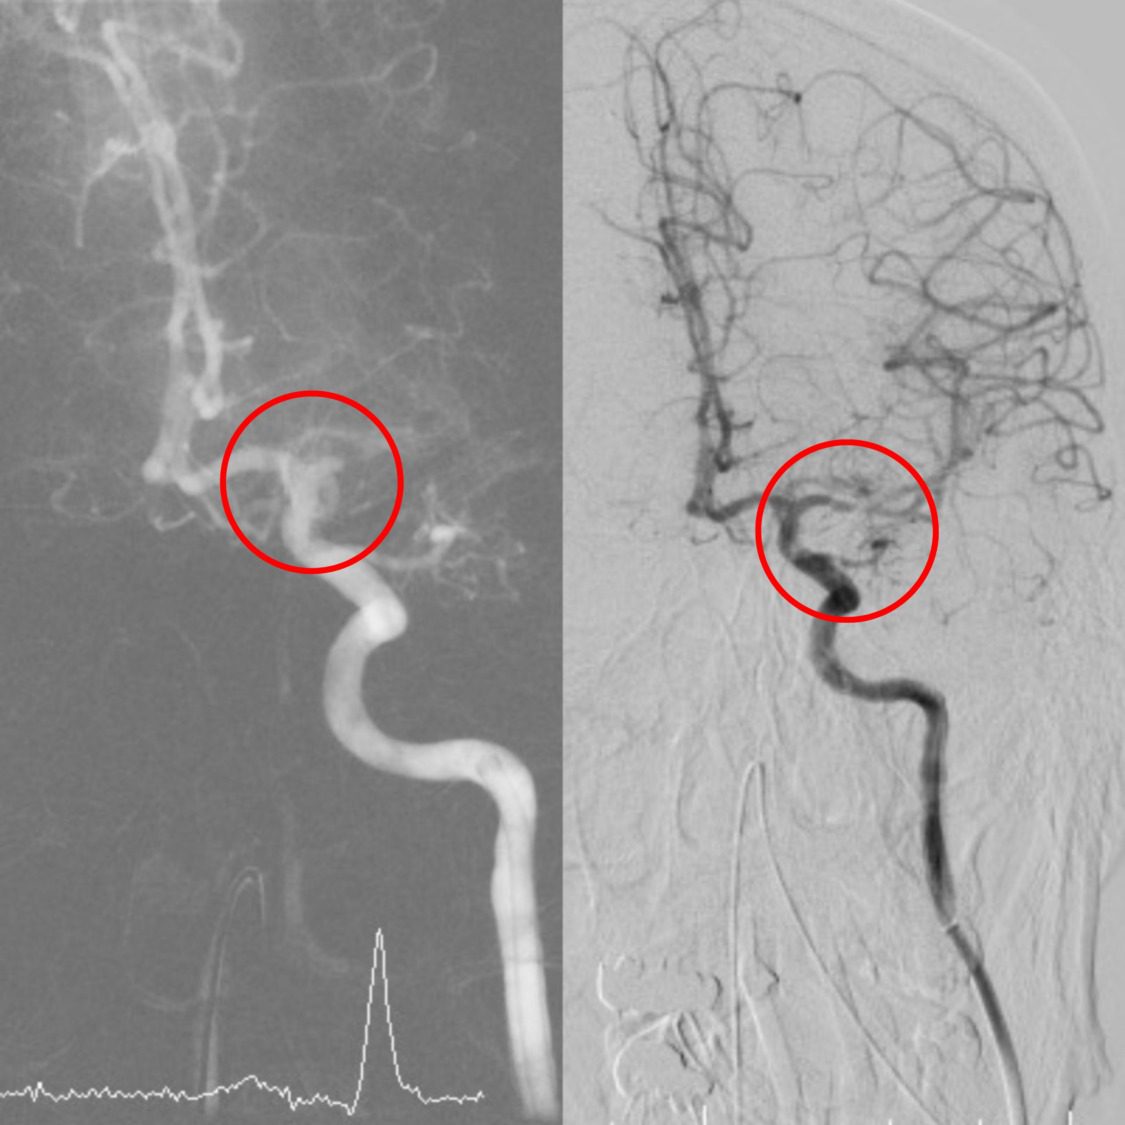

林子超醫師接著說,顱內動脈取栓手術是已經逐漸普及的急性腦導管治療,醫師會從病人鼠蹊部的股動脈進行穿刺,藉由不同的導管組合,將抽吸導管或支架,從下肢動脈逆行到血栓塞住的顱內血管處,將血栓藉由支架取出或負壓吸出,相較於以往的血栓溶解劑治療及保守藥物治療,大血管梗塞的病患在接受顱內動脈取栓手術後,能獲得更積極的治療效果以及更好的預後。

2023年11月起,動脈取栓術給付條件也從中風後8小時延長至24小時內,其優點包括(1)在大血管梗塞的中風,提供給病患更積極的治療效果;(2)相較於血栓溶解劑治療,可治療病情更嚴重、送達急診時間更久的中風病患;(3)在執行手術過程中,可直接探查病患血管狀況,並發現其他隱藏的血管性病灶,如血管壁剝離、血管瘤或動靜脈畸形等。